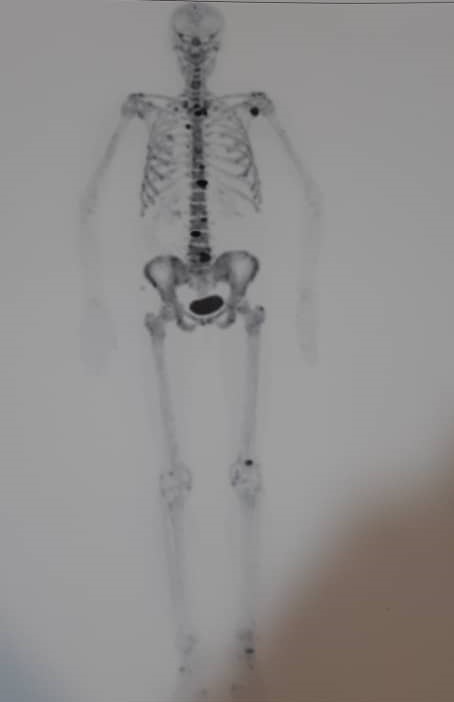

این رادیو داروی که با خلوص بالایی 99 درصد موفق به تولید آن شدیم، جهت تشخیص طیف وسیعی از بیماری های خوش خیم و بدخیم استخوانی، تحت عنوان اسکن استخوان (Bone Scan) با دستگاه PET/CT مورد استفاده قرار می گیرد. این رادیودارو هم به صورت تزریق وریدی و هم به صورت خوراکی ( در افرادی که مشکل تزریق وریدی وجود دارد) می تواند مورد استفاده قرار گیرد.

از مهم ترین بیماری های خوش خیم استخوانی قابل تشخیص با این رادیودارو عبارتند از: استئوپروزیس (پوکی استخوان)، استئومیلیت (التهاب استخوانی)، شکستگی های مخفی استخوانی، عفونت های مخفی استخوانی، اسپوندیلوزیس ستون فقرات ، اسپاندیلولیزیس ( بیماری مهره ای استخوان)، بیماری استخوانی که با روش اسکن های متداول سی تی قابل تشخیص نمی باشند و..

از مهم ترین بیماری های بدخیم استخوانی قابل تشخیص با این رادیودارو عبارتند از: استئوسارکوما (سرطان استخوان)، متاستاز های استخوانی، متاستاز سایر ارگان تومورهای به استخوان (متاستاز سرطان پروستات به استخوان ها) و... می باشد.